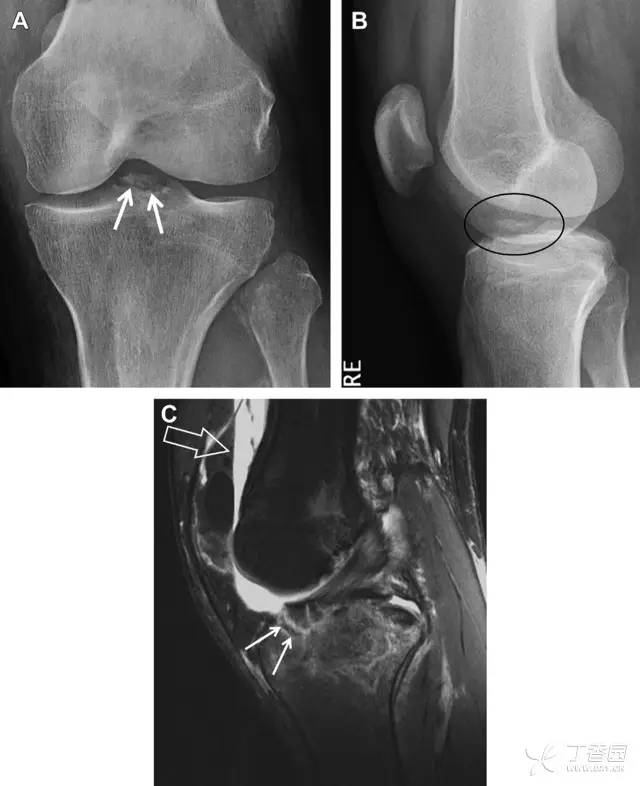

前交叉韧带撕脱骨折常发生在胫骨髁间嵴(图 1)。这种骨折在青少年中常见,但在成年人中也并不像大家想象的那么少见。

图 1 摩托车事故患者前交叉韧带撕脱性骨折

A 正位片示胫骨髁间嵴底部骨折(箭头),注意别把这个骨折碎片错认为关节内结构。B 侧位片示胫骨上方可见一细长型骨折碎片(椭圆)。C MRI 矢状位 T2 加权像示前交叉韧带附着于撕脱的骨折碎片上(箭头),注意周围存在骨髓水肿和积脂血征(空箭头)。